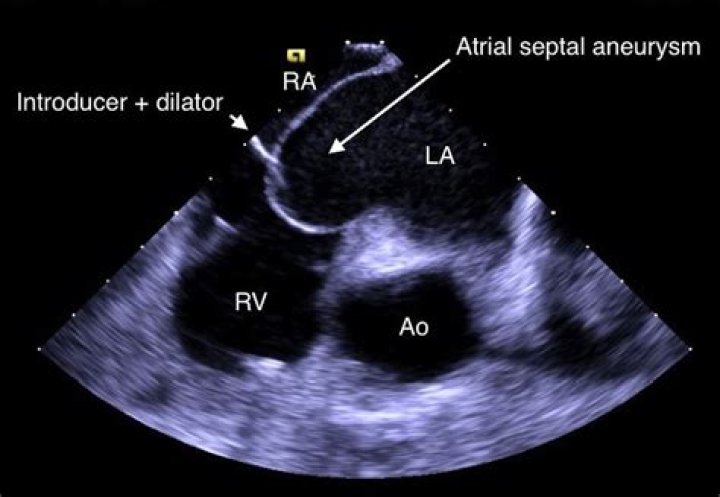

What is aneurysmal interatrial septum?

The interatrial septum is the thin wall that separates the upper atrial cavities of heart. When it appears elongated and “floppy” on cardiac ultrasound, we call it “aneurysmal”. This is a condition that some people are born with. It alone portends no prognostic risk.

An aneurysm of the interatrial septum is an infrequent finding in adult patients. Atrial septal aneurysm is a congenital malformation of the septum primum layer of the interatrial septum but differences between interatrial pressure forces have also been reported as a cause of its development.

Introduction. Atrial septal aneurysm (ASA) is a congenital deformity of interatrial septum consisting redundant and mobile interatrial septal tissue in the region of fossa ovalis with bulging into the right or left atrium and sometimes oscillating between both atria.